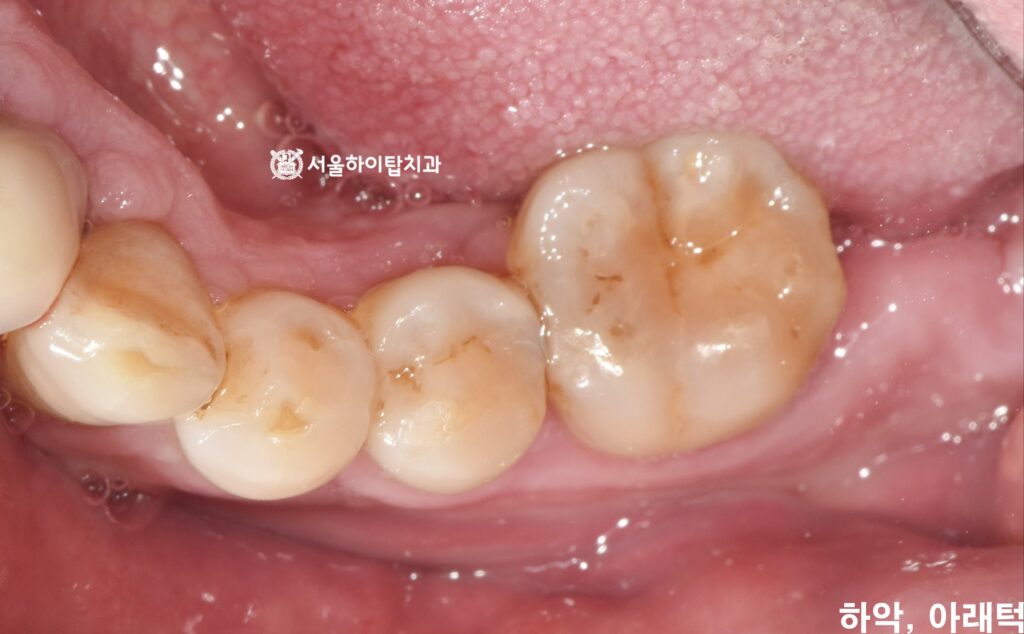

1. 초진

간석역 치과 에서는

한눈에 보더라도 상, 하악 어금니가

상실된 모습을 확인할 수 있습니다.

특히 위턱 부위의 치조골이

상당히 흡수된 모습이 관찰되며,

이는 장기간 기능을 하지 못한 치아

부위에서 흔히 나타나는 변화입니다.

구강 내 임상 사진에서도

짧아진 치근과 치조골 소실로 인해

치근 일부가 외부로 노출된 양상을

확인할 수 있습니다.

더불어, 현재 전체적인 잇몸 건강도

양호하지 않은 상태이기 때문에

지속적인 자가 관리와 정기검진이

반드시 필요한 소견입니다.